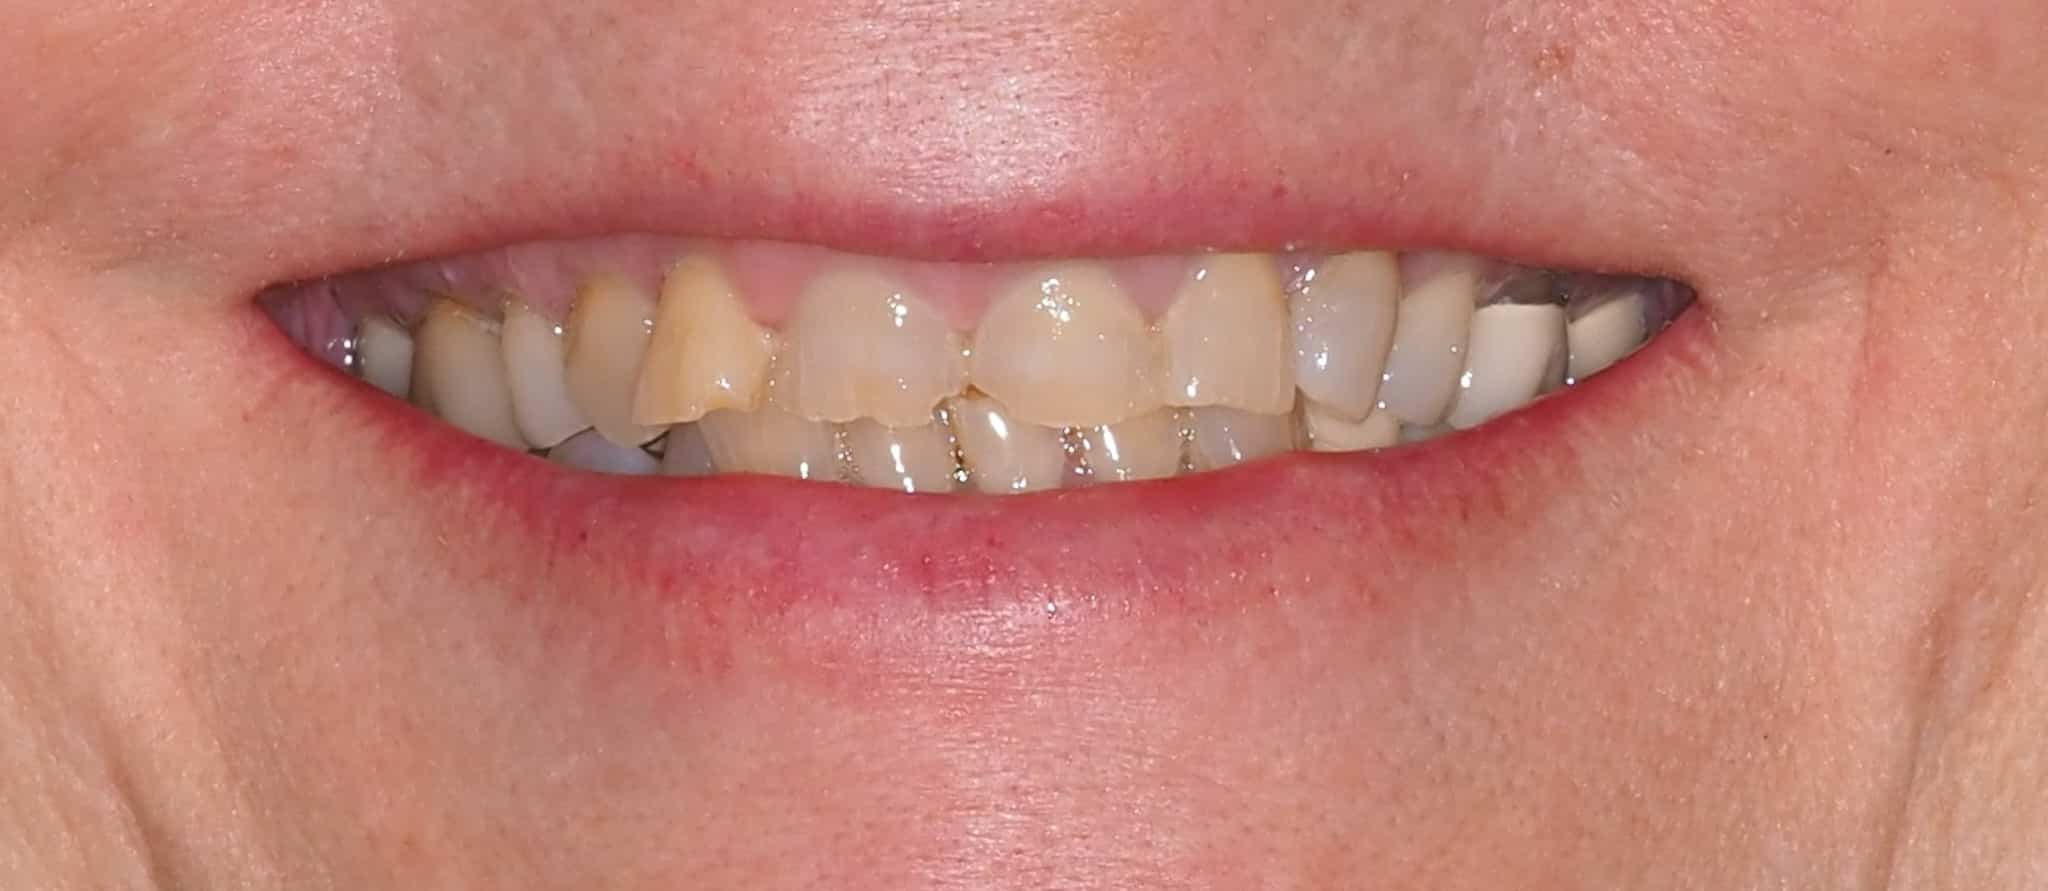

Before and After Image Gallery